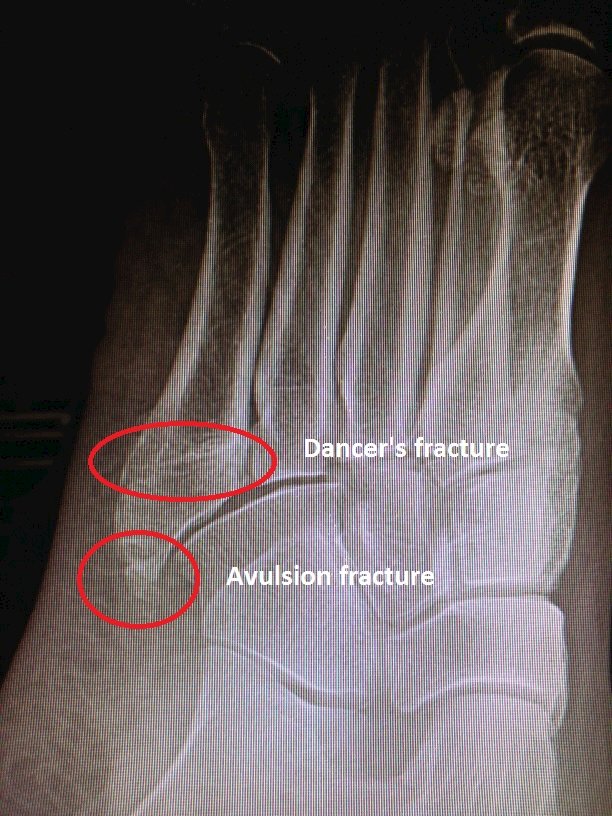

I am 6 weeks post surgery on my 5th displaced metatarsal fracture. I had the hard aircast pump up boot on for 6 weeks. Very rarely is it necessary to operate on these fractures acutely. Fractures to the shaft of the 5th metatarsal shaft are often referred to as dancer's fractures. If not displaced or comminuted, these fractures uniformly heal well with.

5th Metatarsal Shaft "Dancer's" Fracture - FootEducation from footeducation.com Usually there is no need for surgery; Distal radius fractures programme online course: Formulary drug information for this topic. Metatarsal fracture avulsion fracture stress fracture jones fracture bow legged sprained ankle foot pain videos funny surgery. Acute diaphyseal fractures tend to occur near the metaphysis and the mechanism is usually a crush injury or an inversion force that causes avulsion by the peroneus brevis tendon. A 5th metatarsal avulsion fracture is often confused with a 5th metatarsal metadiaphyseal stress fracture (jones fracture). Surgery might be needed if the avulsion fracture is displaced. Unlike a dancer's fracture, a jones fracture will more commonly fail to heal without surgery despite extended periods of non weight bearing.

Fractures to the shaft of the 5th metatarsal shaft are often referred to as dancer's fractures. Avulsion 5th metatarsal base fracture. In an avulsion fracture, a small piece of bone is pulled off the main portion of the bone by a other types of fractures can occur in the fifth metatarsal. The doctor can use a cast or other method to hold the injured foot in place while the fracture recovers. While this injury needs to be distinguished from. Swiss surgery = schweizer chirurgie = chirurgie suisse = chirurgia svizzera. Formulary drug information for this topic. The 5th metatarsal is the outer bone that connects to your little an avulsion fracture occurs when a tendon pulls a piece of bone away from the rest of the bone. This can occur at the ligament by the application of forces external to the body (such as a fall or pull). There are five metatarsal bones in your foot. I rolled my ankle on 5 october and broke 4th and 5th. Treatment is either immobilization or surgery depending on location of fracture, degree of displacement, and athletic level of patient. A small piece of bone is pulled off the main portion of the bone by a tendon or ligament.

Tuberosity avulsion fracture, jones fracture and diaphyseal stress fracture:all three fractures cause lateral foot pain and difficulty walking.

Management of distal radius fractures programme. Fifth metatarsal fracture, proximal fifth metatarsal fracture, jones fracture, fifth metatarsal base fracture. Avulsion fractures of the fifth metatarsal base: When there is significant displacement a in rare situations it may be necessary to undertake reconstructive surgery which would repair not only the fracture (often with bone grafting). A 5th metatarsal avulsion fracture is often confused with a 5th metatarsal metadiaphyseal stress fracture (jones fracture). I saw my foot doctor for the broken bone. Posted 7 years ago, 149 users are following. A small piece of bone is pulled off the main portion of the bone by a tendon or ligament. Fifth metatarsal fractures are notoriously slow healing fractures, but after ten weeks, especially since you had surgery, under most circumstances you. Fractures of the proximal fifth metatarsal pose an important diagnostic challenge. Treatment is either immobilization or surgery depending on location of fracture, degree of displacement, and athletic level of patient. Jones fracture is a difficult fracture to heal due to limited blood supply to that area and often surgery. Traditionally this avulsion fracture has been ascribed to the insertion of peroneus brevis and is caused by forcible inversion of the foot in plantar flexion radiographic features.